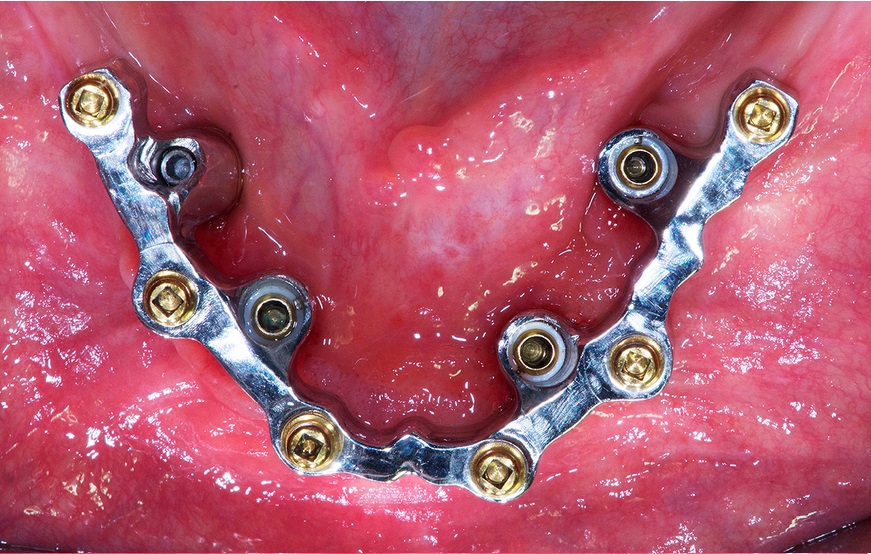

Streszczenie: Artykuł przedstawia przypadek leczenia całkowicie bezzębnego pacjenta za pomocą overdenture na tytanowej belce (CAD/CAM) utrzymywanym przez zatrzaski niskoprofilowe.

Summary: The article presents a case of the treatment of a completely toothless patient by means of an overdenture on a titanium beam (CAD/CAM) held by low-profile latches.

Rehabilitacja protetyczno-implantologiczna z implantami dentystycznymi u pacjentów z VI klasą Cawooda i Howella nadal stanowi duże wyzwanie. Przedstawiony przypadek pokazuje, jak ważną opcją rehabilitacji u pacjentów z atrofią jest „pasywne” overdenture na tytanowej belce (CAD/CAM) utrzymywane przez zatrzaski niskoprofilowe. Ten przypadek kliniczny przedstawia krok po kroku rehabilitację całkowicie bezzębnego pacjenta (65 lat). Zabieg obejmuje tomografię komputerową Cone Beam z protokołem podwójnego skanowania, umieszczenie czterech implantów w ramach chirurgii kierowanej, a następnie produkcję tytanowej belki CAD/CAM z niskoprofilowymi zatrzaskami do utrzymania nadbudowy wykonanej ze stopu [...]